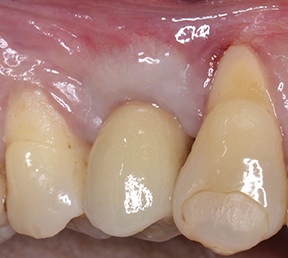

At the end of the osseointegration period, the implant was uncovered and the healing abutment placed. Following soft-tissue conditioning by means of a provisional crown (Fig. 26), a metal-ceramic crown was cemented onto the prosthetic abutment (Fig. 27).

Fig. 26: Soft-tissue conditioning with a provisional crown

Block by Block

Fig. 27: Final metal-ceramic crown cemented onto the prosthetic abutment